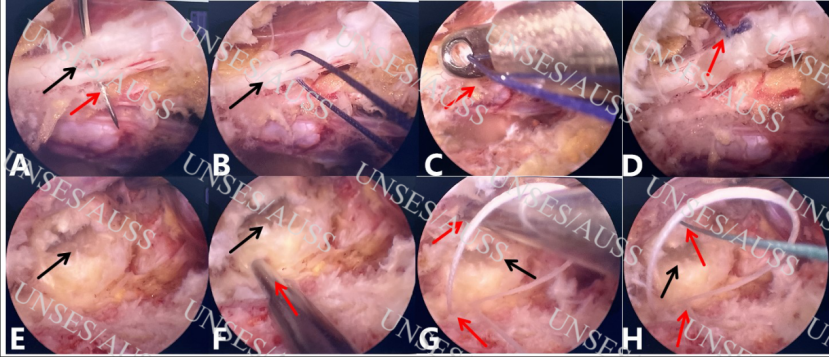

图2 硬膜囊缝合,纤维环“井”字型四针缝合手术步骤(1)A-B 硬膜囊破口,应用4-0可吸收带线针,垂直于硬膜囊破口进行硬膜囊撕裂处缝合;C-D由体外至体内打三结,推结器推结,剪线器剪线;E暴露突出间盘,摘除突出间盘,见纤维环破口;F应用白色带线环纤维环缝合器于距纤维环破口外侧(关节突侧)2mm处进针,推入线棒,拔出缝合器,可见白色线环;G应用第二根绿线纤维环缝合器穿入白色线环内,在距纤维环破口内侧(中线侧)2mm处进针;H推入线棒,拔出缝合器后可见绿线在白色线环内。